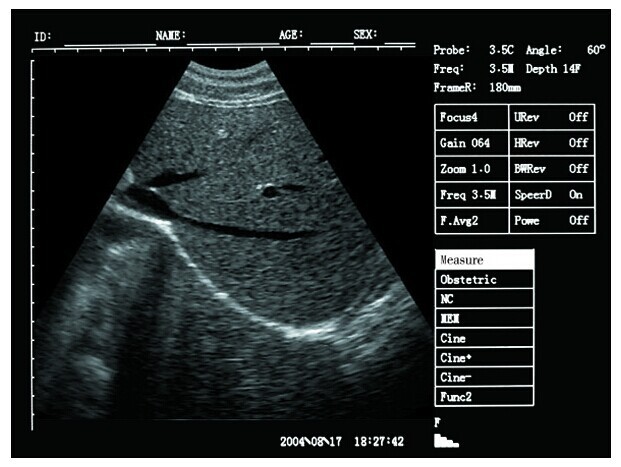

Portable ultrasound machine Laptop Ultrasound machine SU-7S with CE Images |